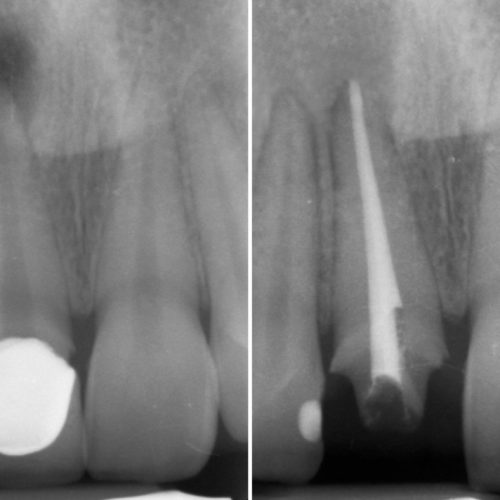

ApprofondisciENDODONZIA

L’Endodonzia è quella specializzazione dell’Odontoiatria che si occupa della terapia dell’endodonto, cioè dello spazio all’interno del dente che contiene la Polpa Dentaria (nervi e vasi sanguigni).